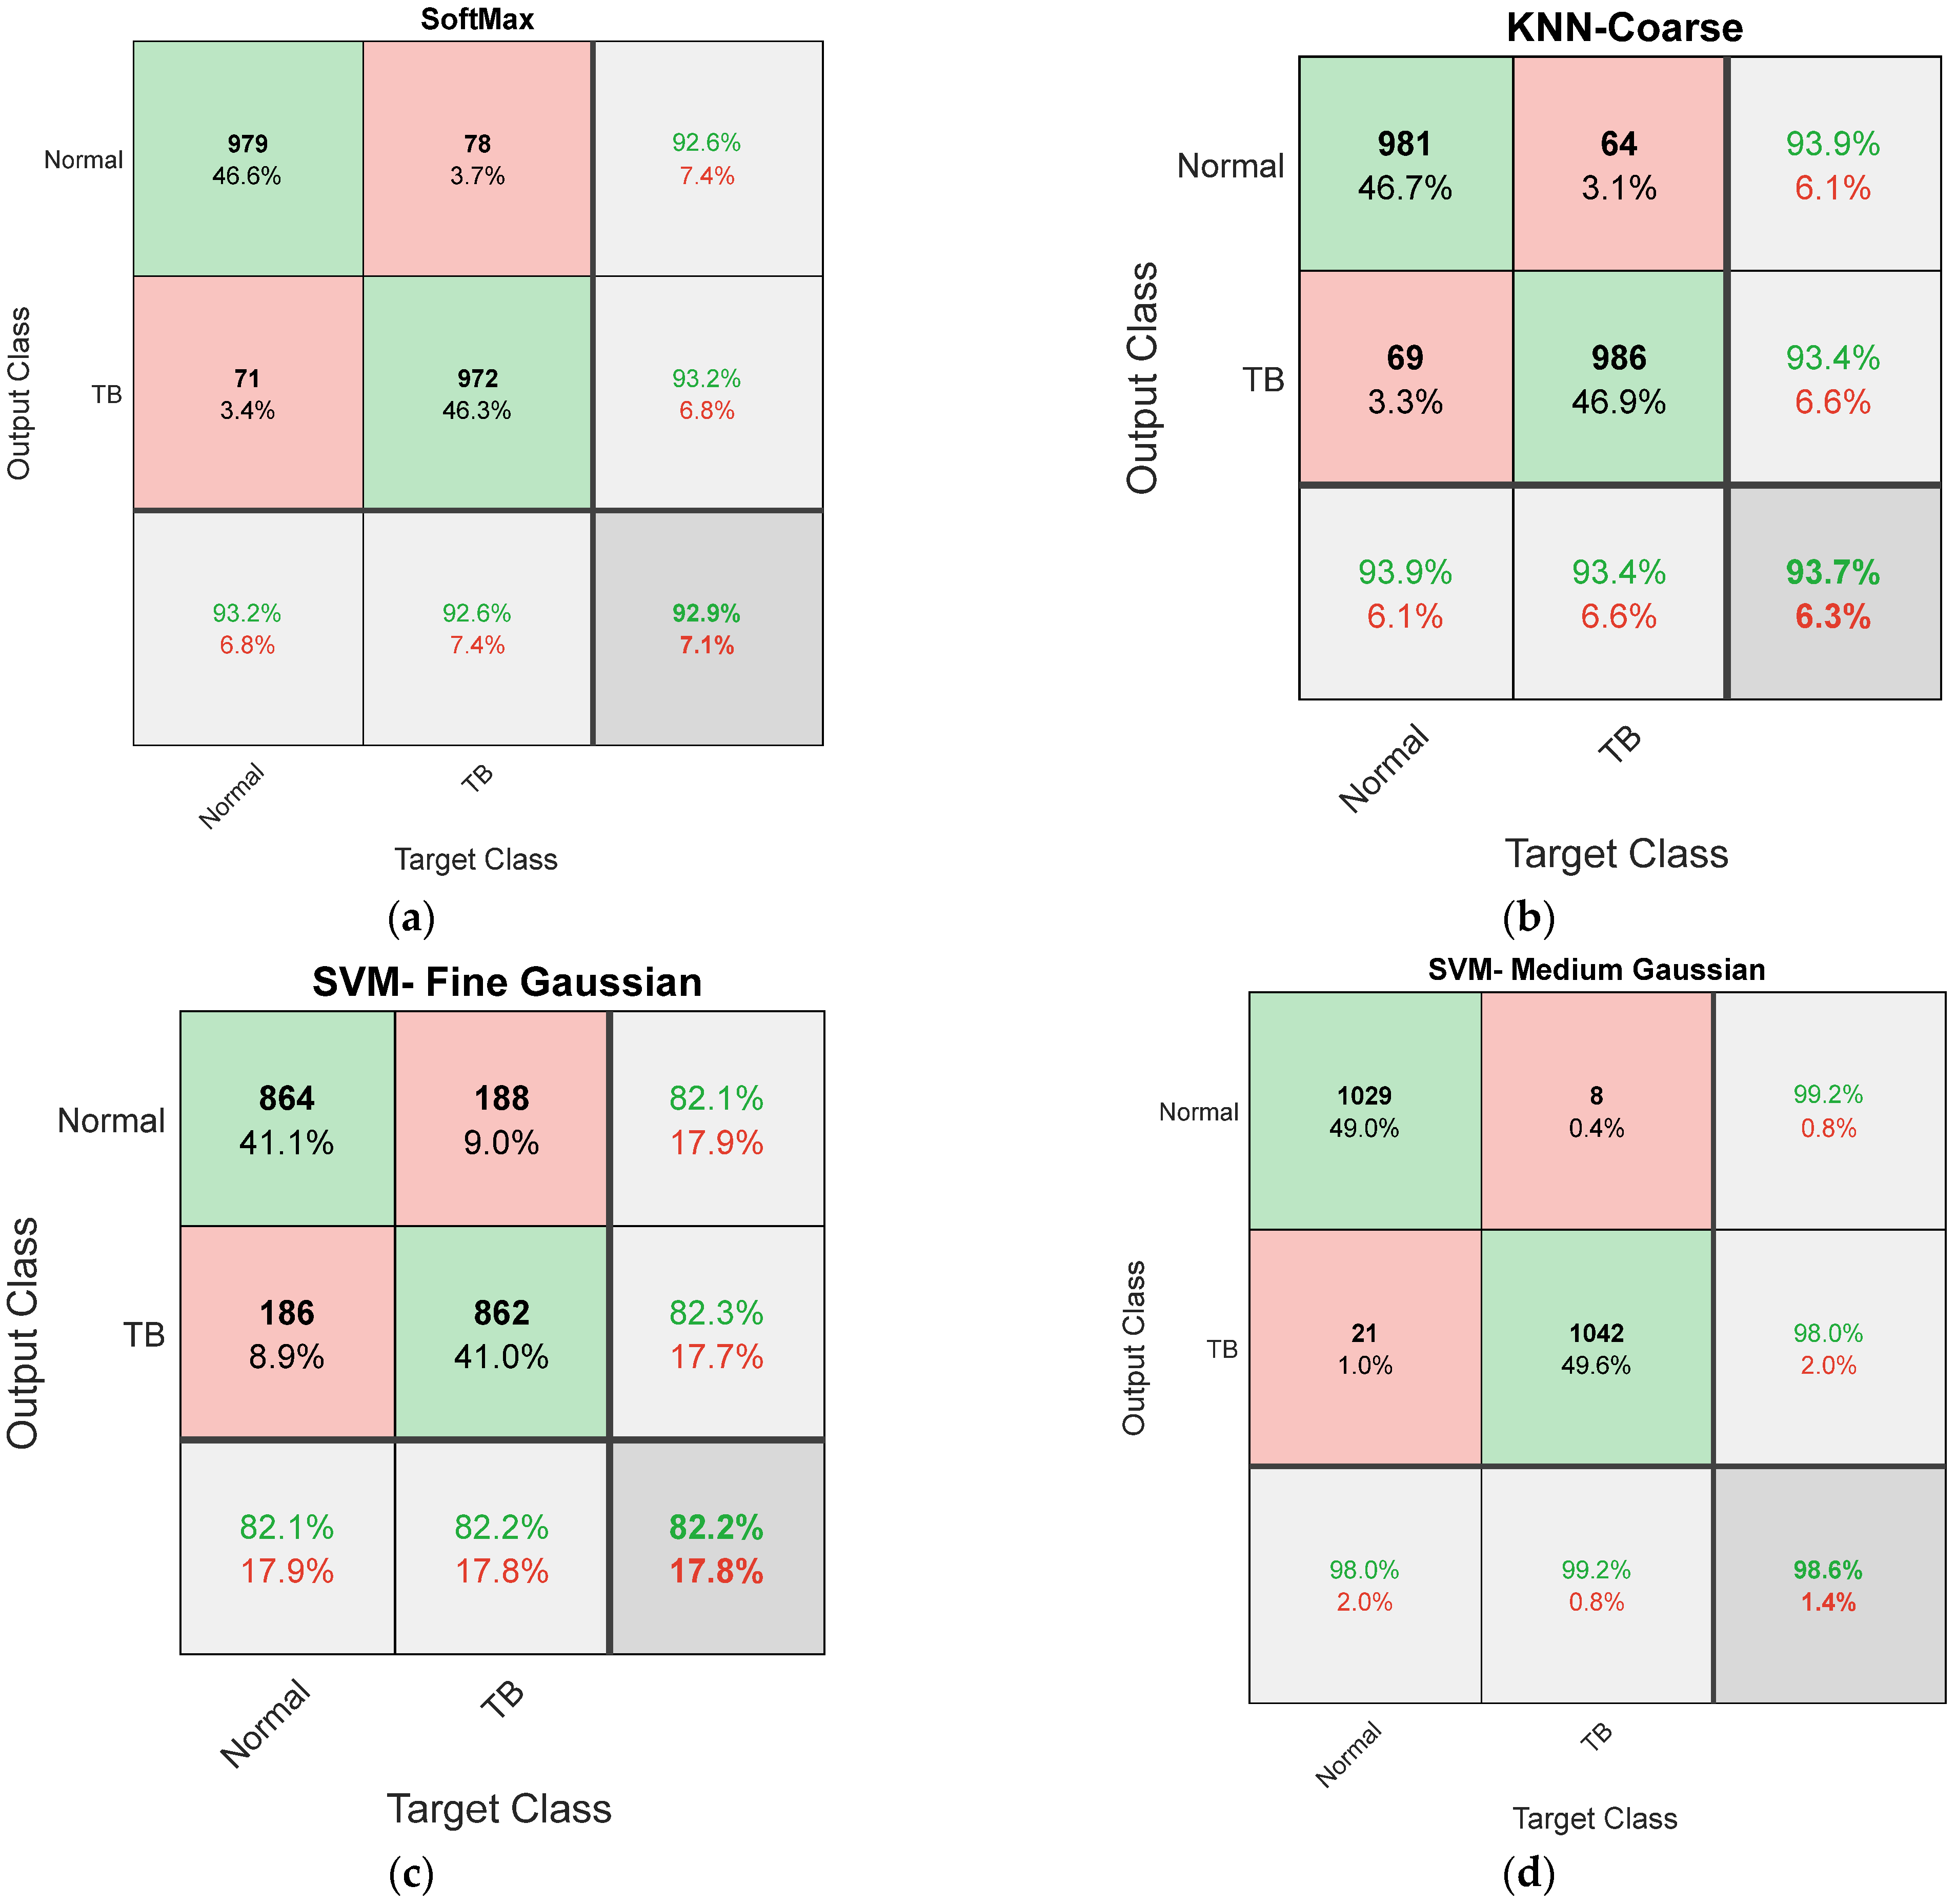

| Feature | Classifier | TP | FN | TN | FP | ACC% | PRE% | SEN% | SPE% | NPV% |

|---|---|---|---|---|---|---|---|---|---|---|

| DLF | SoftMax | 973 | 77 | 978 | 72 | 92.9048 | 93.1100 | 92.6667 | 93.1429 | 92.7014 |

| Gaussian Naive Bayes | 975 | 75 | 980 | 70 | 93.0952 | 93.3014 | 92.8571 | 93.3333 | 92.8910 | |

| Logistic Regression | 976 | 74 | 976 | 74 | 92.9524 | 92.9524 | 92.9524 | 92.9524 | 92.9524 | |

| DT-Coarse | 982 | 68 | 979 | 71 | 93.3810 | 93.2574 | 93.5238 | 93.2381 | 93.5053 | |

| DT-Medium | 981 | 69 | 983 | 67 | 93.5238 | 93.6069 | 93.4286 | 93.6190 | 93.4411 | |

| DT-Fine | 978 | 72 | 980 | 70 | 93.2381 | 93.3206 | 93.1429 | 93.3333 | 93.1559 | |

| KNN-Coarse | 981 | 69 | 986 | 64 | 93.6667 | 93.8756 | 93.4286 | 93.9048 | 93.4597 | |

| KNN-Medium | 974 | 76 | 979 | 71 | 93.0000 | 93.2057 | 92.7619 | 93.2381 | 92.7962 | |

| KNN-Fine | 977 | 73 | 982 | 68 | 93.2857 | 93.4928 | 93.0476 | 93.5238 | 93.0806 | |

| SVM-Linear | 982 | 68 | 977 | 73 | 93.2857 | 93.0806 | 93.5238 | 93.0476 | 93.4928 | |

| SVM-Coarse Gaussian | 980 | 70 | 983 | 67 | 93.4762 | 93.6008 | 93.3333 | 93.6190 | 93.3523 | |

| SVM-Medium Gaussian | 979 | 71 | 977 | 73 | 93.1429 | 93.0608 | 93.2381 | 93.0476 | 93.2252 | |

| SVM-Fine Gaussian | 982 | 68 | 981 | 69 | 93.4762 | 93.4348 | 93.5238 | 93.4286 | 93.5176 | |

| MLF | SoftMax | 841 | 209 | 864 | 186 | 81.1905 | 81.8890 | 80.0952 | 82.2857 | 80.5219 |

| Gaussian Naive Bayes | 853 | 197 | 848 | 202 | 81.0000 | 80.8531 | 81.2381 | 80.7619 | 81.1483 | |

| Logistic Regression | 856 | 194 | 851 | 199 | 81.2857 | 81.1374 | 81.5238 | 81.0476 | 81.4354 | |

| DT-Coarse | 849 | 201 | 862 | 188 | 81.4762 | 81.8708 | 80.8571 | 82.0952 | 81.0913 | |

| DT-Medium | 853 | 197 | 859 | 191 | 81.5238 | 81.7050 | 81.2381 | 81.8095 | 81.3447 | |

| DT-Fine | 863 | 187 | 861 | 189 | 82.0952 | 82.0342 | 82.1905 | 82.0000 | 82.1565 | |

| KNN-Coarse | 865 | 185 | 852 | 198 | 81.7619 | 81.3735 | 82.3810 | 81.1429 | 82.1601 | |

| KNN-Medium | 862 | 188 | 861 | 189 | 82.0476 | 82.0171 | 82.0952 | 82.0000 | 82.0782 | |

| KNN-Fine | 857 | 193 | 864 | 186 | 81.9524 | 82.1668 | 81.6190 | 82.2857 | 81.7408 | |

| SVM-Linear | 853 | 197 | 863 | 187 | 81.7143 | 82.0192 | 81.2381 | 82.1905 | 81.4151 | |

| SVM-Coarse Gaussian | 858 | 192 | 862 | 188 | 81.9048 | 82.0268 | 81.7143 | 82.0952 | 81.7837 | |

| SVM-Medium Gaussian | 861 | 189 | 864 | 186 | 82.1429 | 82.2350 | 82.0000 | 82.2857 | 82.0513 | |

| SVM-Fine Gaussian | 864 | 186 | 862 | 188 | 82.1905 | 82.1293 | 82.2857 | 82.0952 | 82.2519 |

| Classifier | TP | FN | TN | FP | ACC% | PRE% | SEN% | SPE% | NPV% |

|---|---|---|---|---|---|---|---|---|---|

| SoftMax | 993 | 57 | 1004 | 46 | 95.0952 | 95.5727 | 94.5714 | 95.6190 | 94.6277 |

| Gaussian Naive Bayes | 1026 | 24 | 1015 | 35 | 97.1905 | 96.7012 | 97.7143 | 96.6667 | 97.6901 |

| Logistic Regression | 1031 | 19 | 1022 | 28 | 97.7619 | 97.3560 | 98.1905 | 97.3333 | 98.1748 |

| DT-Coarse | 995 | 55 | 993 | 57 | 94.6667 | 94.5817 | 94.7619 | 94.5714 | 94.7519 |

| DT-Medium | 1018 | 32 | 1023 | 27 | 97.1905 | 97.4163 | 96.9524 | 97.4286 | 96.9668 |

| DT-Fine | 1007 | 43 | 1002 | 48 | 95.6667 | 95.4502 | 95.9048 | 95.4286 | 95.8852 |

| KNN-Coarse | 1018 | 32 | 1007 | 43 | 96.4286 | 95.9472 | 96.9524 | 95.9048 | 96.9201 |

| KNN-Medium | 1002 | 48 | 1001 | 49 | 95.3810 | 95.3378 | 95.4286 | 95.3333 | 95.4242 |

| KNN-Fine | 1037 | 13 | 1029 | 21 | 98.3810 | 98.0151 | 98.7619 | 98.0000 | 98.7524 |

| SVM-Linear | 1007 | 43 | 992 | 58 | 95.1905 | 94.5540 | 95.9048 | 94.4762 | 95.8454 |

| SVM-Coarse Gaussian | 1013 | 37 | 1009 | 41 | 96.2857 | 96.1101 | 96.4762 | 96.0952 | 96.4627 |

| SVM-Medium Gaussian | 1029 | 21 | 1042 | 8 | 98.6190 | 99.2285 | 98.0000 | 99.2381 | 98.0245 |

| SVM-Fine Gaussian | 1031 | 19 | 1036 | 14 | 98.4286 | 98.6603 | 98.1905 | 98.6667 | 98.1991 |